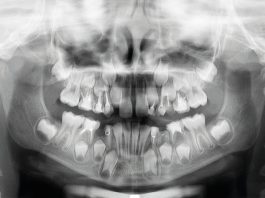

Malocclusione di classe II con morso profondo e lieve affollamento superiore anteriore trattata con...

La malocclusione di classe II può essere distinta in scheletrica e dentale. La malocclusione scheletrica di classe II si riferisce più spesso a una...

Gestione ortodontica di una malocclusione di II classe scheletrica con il dispositivo di avanzamento...

La terapia ortodontica durante la prima dentizione riveste un ruolo fondamentale nell'ambito dell'attuale pratica odontoiatrica. Il suo scopo primario è eliminare i fattori ritenuti...